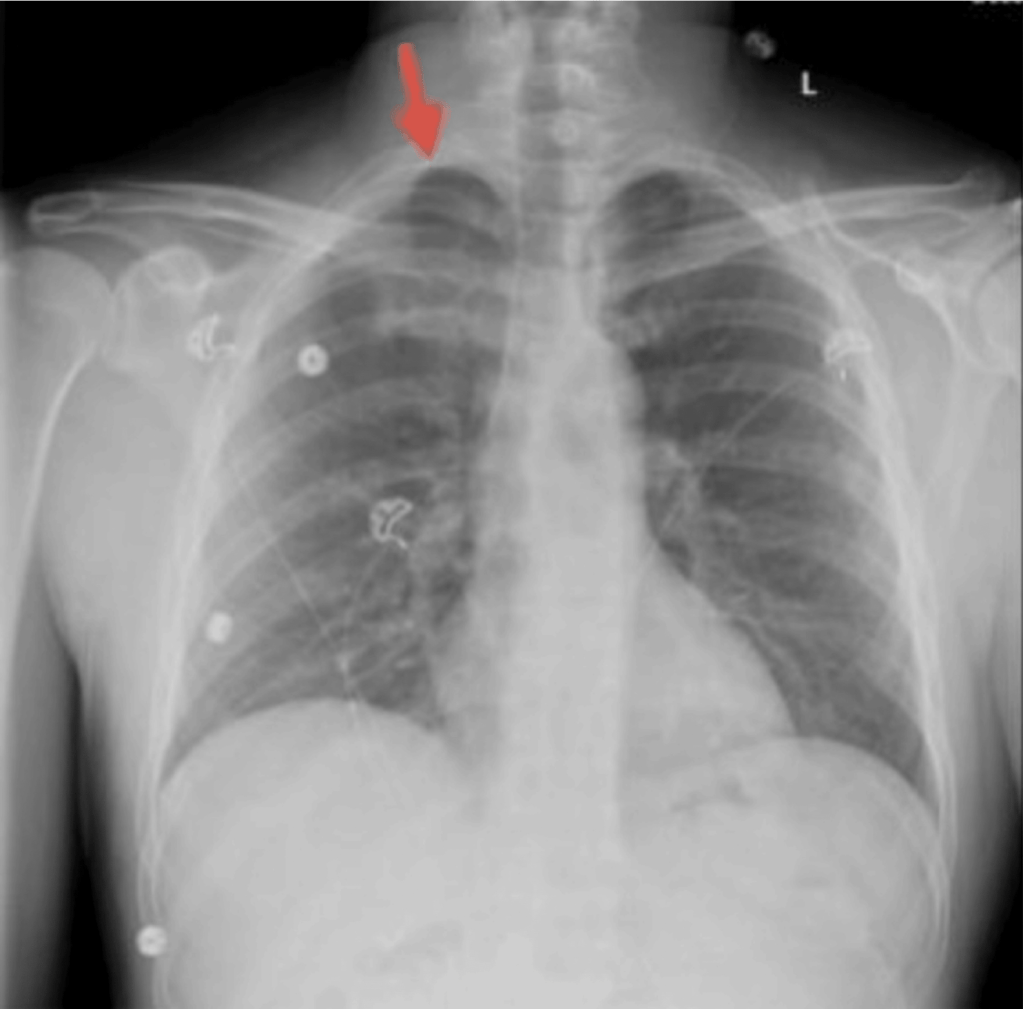

The patient developed right sided back pain that was worse on inspiration some 2.5 hours following the TPIs. He was relatively stable on admission and had a small right apical pneumothorax. A metallic foreign body was seen in the lower right chest field, and this was removed using VATS.